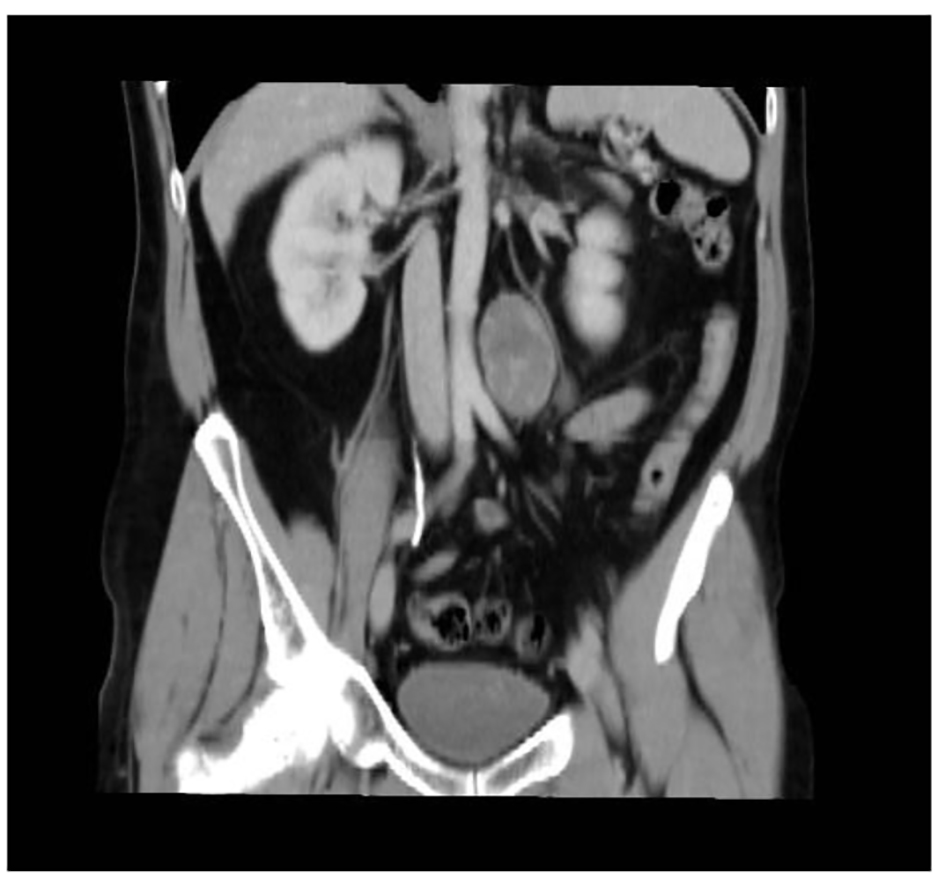

A 46-year-old male smoker with rheumatoid arthritis presented with right iliac fossa pain without other symptoms. CT revealed a 5 × 3.7 cm retroperitoneal mass located in the periaortic area, down left kidney (Fig. 6). Microscopically, biopsy showed vimentin, S-100, CD56 and BCL2 positive and negative for desmin, specific muscle actine and CD34. Ki67 activity was 1%. Theses findings were compatible with benign schwannoma. Laparoscopic test was performed. The tumor had a gray-purple surface with irregular areas. It measured 6.8 × 3.5 × 3.5 cm and weighed 40 g (Fig. 7). Histopathological features were thick fibrous capsules with lymphoid nodules surrounding the tumor. Spindle cells with pale cytoplasm were arranged in fascicles. Rare cells showed enlarged hyperchromatic nuclei. Mitotic activity was low (2/10 HPF). Ki67 activity was 20%. The tumor contained lymphocytic and histocytic aggregates. Immunohistochemical analysis showed positive cells at S-100 and SOX-10 and negative for desmin, EMA CytoK CD117, and GCDFP15.

![]() Click for large image | Figure 6. Abdominal CT scan showing the retroperitoneal lesion. |